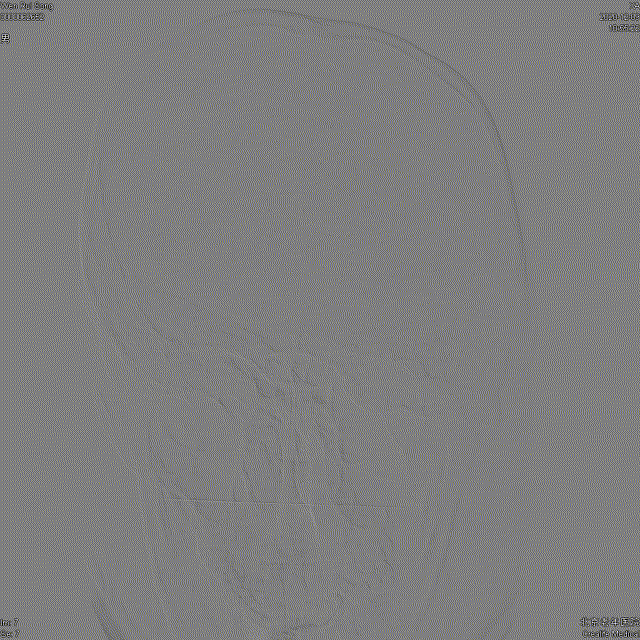

这是颈动脉正位与侧位图,从图中可以看到脑血管造影可以动态、清晰、多方位、多角度的显示血管。